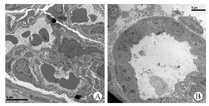

2.Lewis→Balb/c裸小鼠移植后4周,E16Balb/c移植后肾(n=5),呈肾形,质软,输尿管发育良好,内有较多的囊性积尿;皮质和髓质清晰显现。皮质中含红细胞的肾小球、近端小管、远端小管和集合管发育完好,少有淋巴细胞浸润(图1)。电镜显示:肾小球的内皮、系膜和足细胞,基底膜及足突形态结构正常;近端小管和远端小管的上皮细胞,集合管上皮细胞发育良好(图2)。E15Balb/c、E16Balb/c和E17Balb/c三组(n=10)Banff排斥分级差异无统计学意义(P>0.05,表1)。

部分受体鼠切取移植后肾,标本常规苏木素-伊红(HE)染色,光镜下阅片,排斥反应强度参照Banff分类标准[9,10]。部分以质量分数2.5 %戊二醛溶液固定,制作超薄切片,染色,透射电镜(TECNAI 10型)观察。